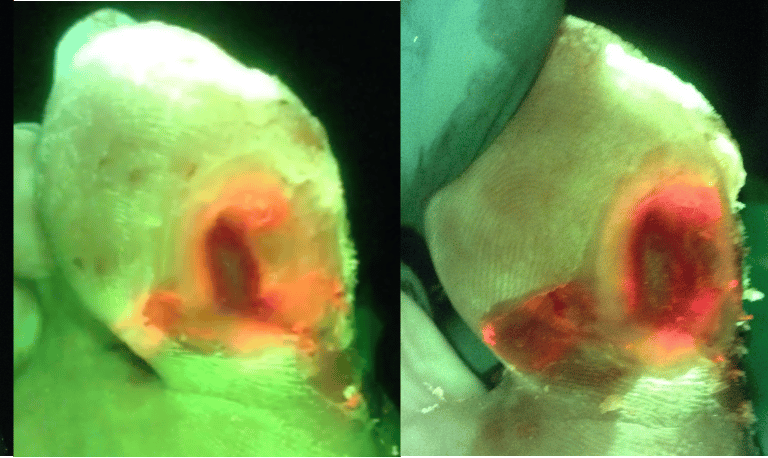

Initial Presentation Undermining Suspected

After Initial Targeted -Aggressive Debridement

Further Debridement Exposes Abscess

After Betadine Soak

Wound Bed Preparation

The foundation for effective wound healing starts with how the wound bed is prepared.

Integration of MolecuLightDX:

real-time imaging for bacterial presence for targeted debridement

digital wound dimension and wound tracking

Integration of XSONX Wound Hygiene System:

vibrational debridement for pain-reduced, effective biofilm removal

uniform debridement & wound edge refashioning

Training on wound bed assessment, viability, and readiness protocols